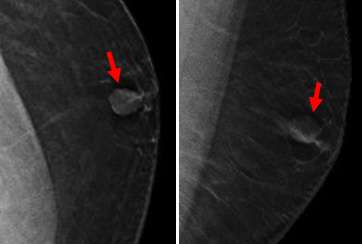

Invasive Ductal Carcinoma

The most common histologic subtype of male breast cancer is invasive ductal carcinoma of no special type (85% of cases)1. On mammography, this often appears as a high-density round, oval or irregular subareolar mass with margins that may be circumscribed, indistinct, spiculated, or microlobulated3. Microcalcifications are seen in 13-30% of cases, less commonly than in females3.

Typically, ultrasound demonstrates a solid, hypoechoic mass. An eccentric location relative to the nipple can be a helpful distinguishing feature from gynecomastia1.